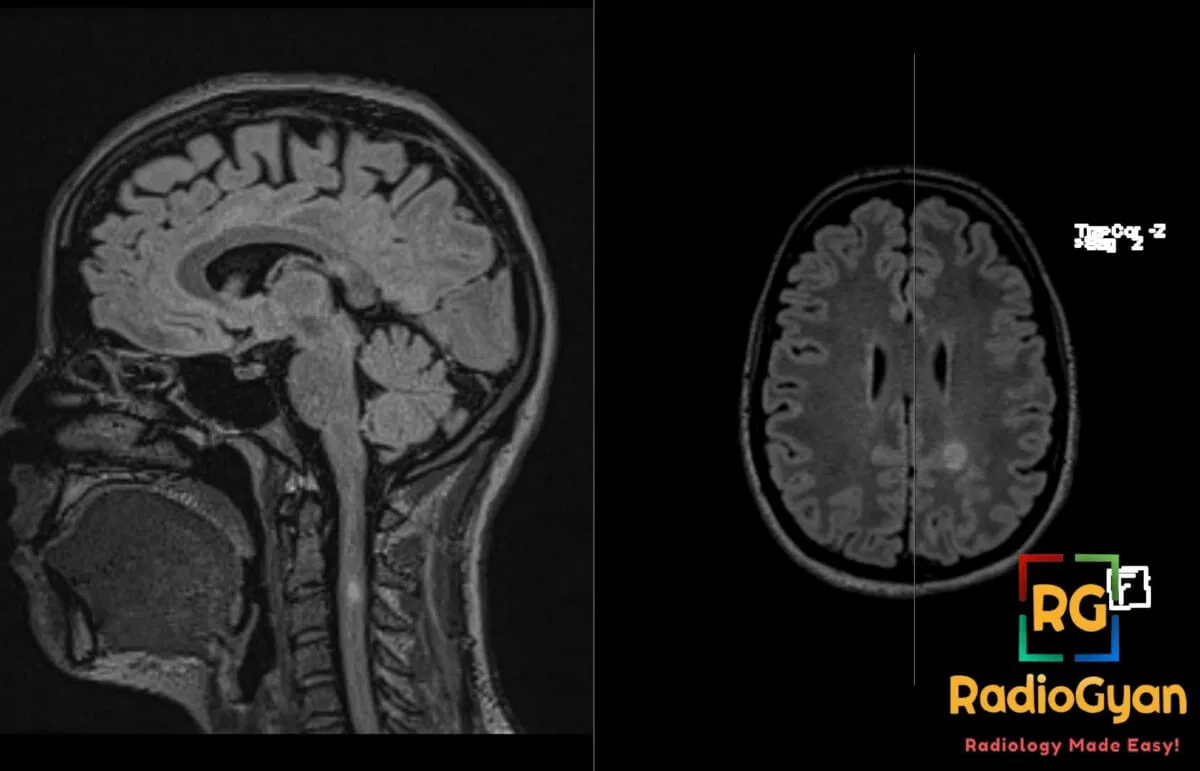

32 yr female presenting with subacute motor weakness and sensory disturbances.

Diagnosis: Multiple sclerosis

- MRI: T2/FLAIR hyperintense lesions in periventricular, juxtacortical, infratentorial, and spinal cord regions; chronic lesions appear as T1 hypointense “black holes”; active lesions show variable gadolinium enhancement; spinal lesions are typically short-segment (less than 2 vertebral levels).

- Signs: Dawson’s fingers (ovoid lesions perpendicular to ventricles); Open-ring enhancement (incomplete enhancement favoring demyelination over tumor); Central vein sign (vein within lesion on susceptibility-weighted imaging); Black holes (axonal loss).